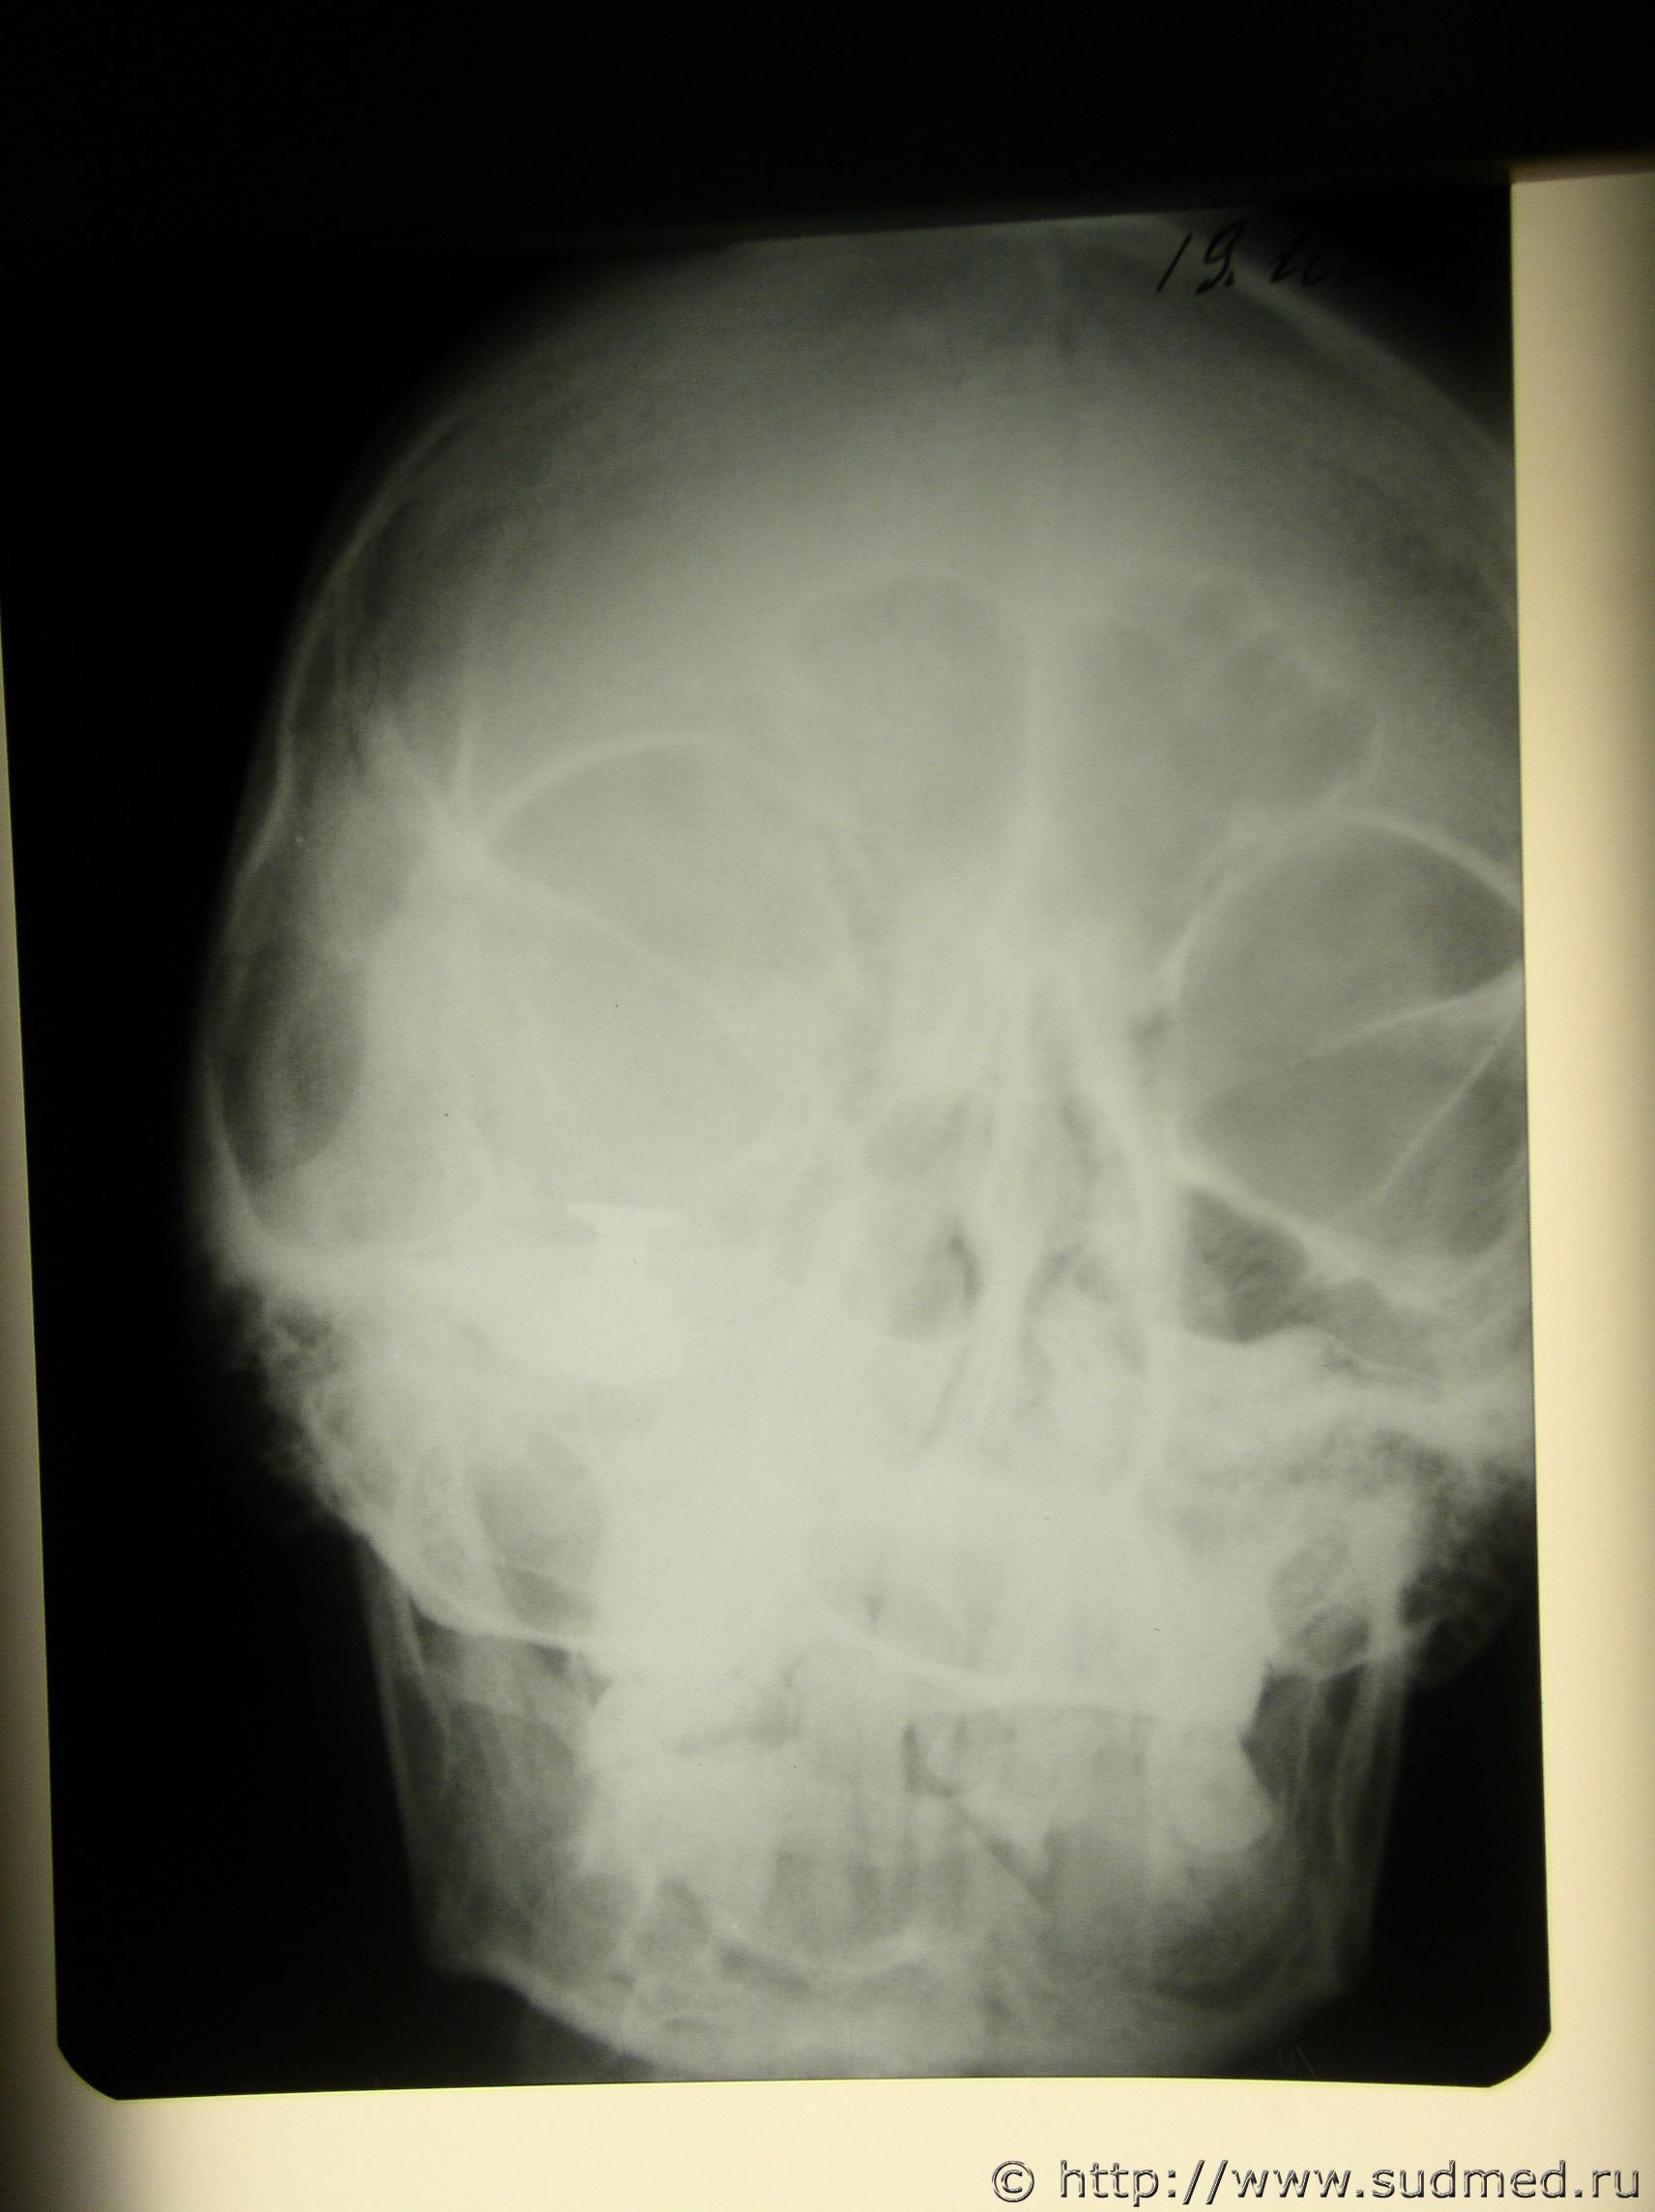

Пуля от "Осы" в мягких тканях лица.

Пуля от "Осы" реальная, была экспертиза по "живым" лицам, добавляю переднюю проекцию рентгена.

Судебная медицина - Прикрепленное изображение Судебная медицина - Прикрепленное изображение